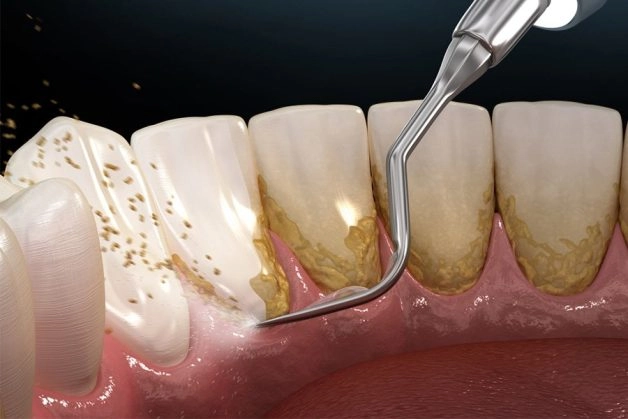

Loại bỏ cao răng cần sử dụng máy móc và dụng cụ chuyên dụng

Với đặc điểm bám cứng tại răng, nhất là những vùng khó làm sạch bằng cách đánh răng, chúng ta không thể tự làm sạch cao răng ngay tại nhà vì làm sai cách có thể gây tổn thương đến răng và nướu. Chính vì vậy việc mà bạn có thể làm để loại bỏ cao răng chính là đến nha sĩ để lấy cao răng bằng máy móc và dụng cụ chuyên dụng. Vậy nhưng lấy cao răng liệu có thực sự cần thiết? Cứ để cao răng vậy có ảnh hưởng gì đến sức khỏe? Hãy cùng tìm hiểu tiếp nhé!